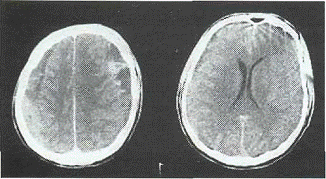

Семиотика. По плотности в единицах Haunsfild ХСГ делятся на

гиподенсивные (28 и менее Ед. Н), изоденсивные (29-45 Ед. Н), гиперденсивные

(более 45 Ед. Н) а также гетероденсивные (рис.4).

Гиподенсивные ХСГ встречаются наиболее

часто. Снижение плотности содержимого гематомы колеблется от выраженного до

незначительного (17-28 Ед. Н), однако всегда превышает плотность ликвора. Чаще

гиподенсивная зона гомогенна (рис.4 а), но порой улавливаются и разные по

интенсивности участки снижения плотности. На этом фоне могут выявляться

линейные повышения плотности за счет визулизации наружного или внутреннего

листка капсулы либо перегородок при многокамерной ХСГ (см. рис.3).

Рис.4. КТ варианты плотностных

характеристик ХСГ: а) гиподеисивыая; б) гипердепсивная; в) изоденсивная; г)

гетеро-дснсивная;